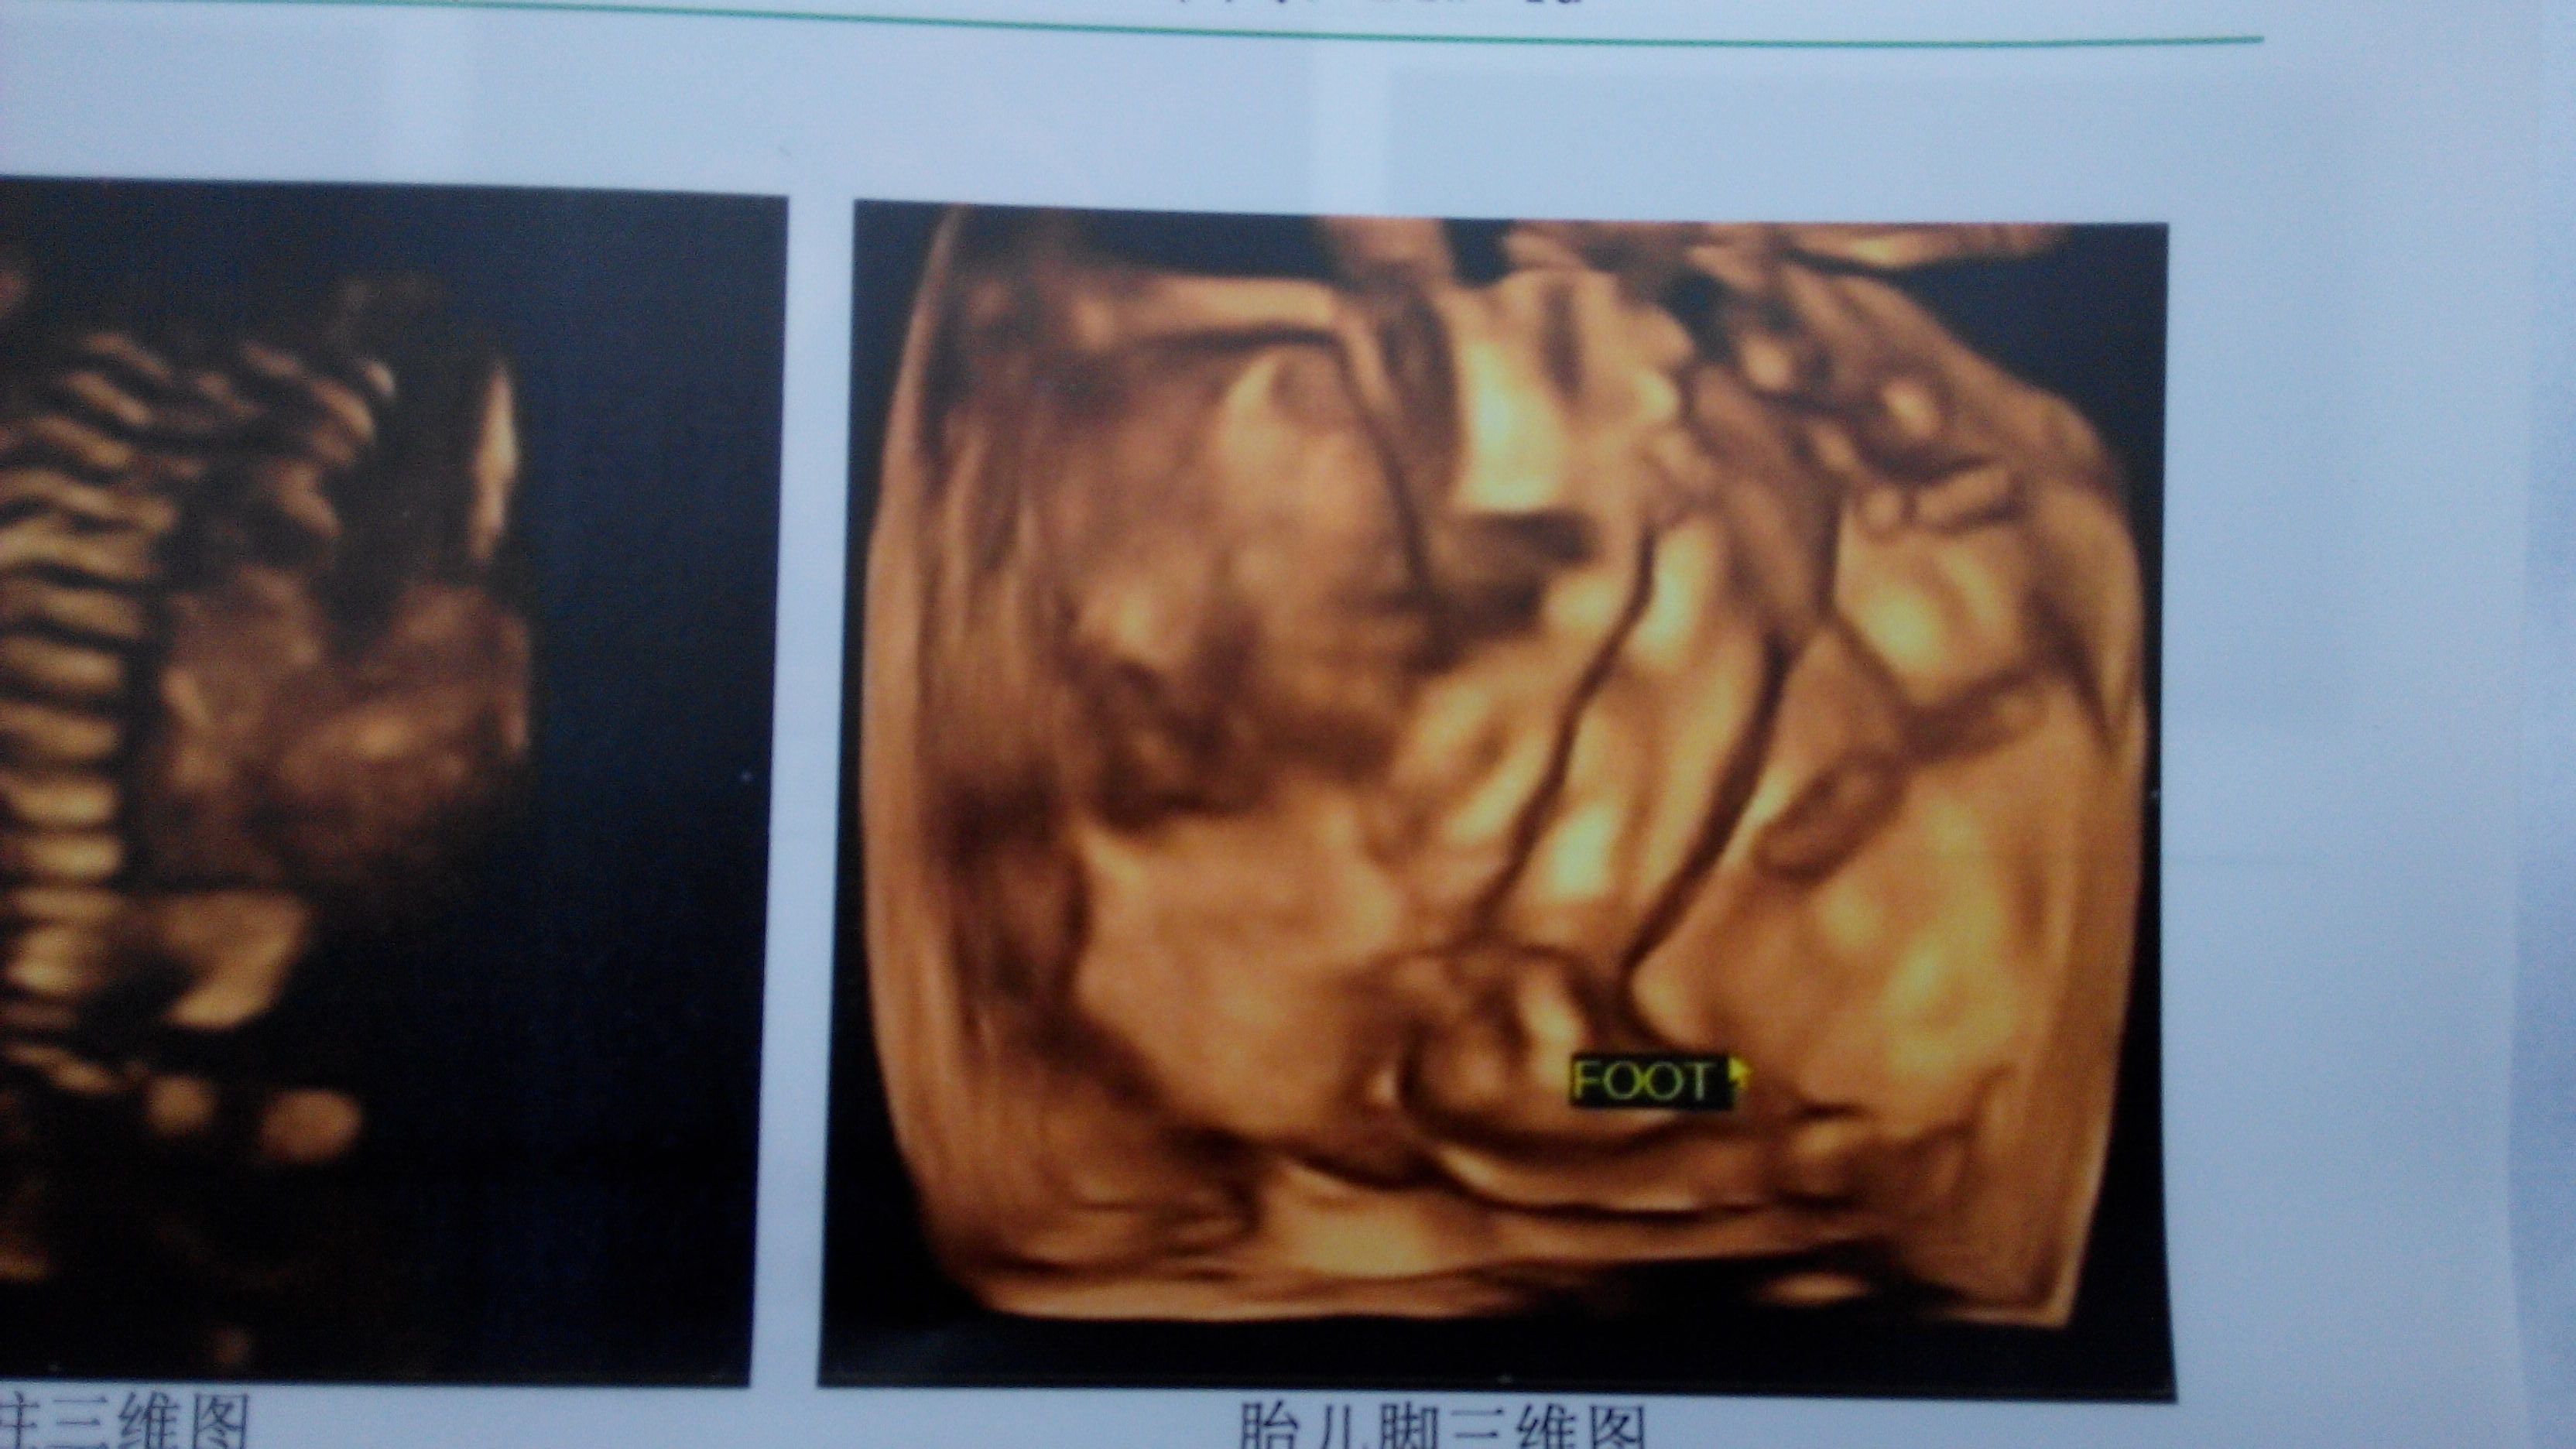

帮忙看一下这张四维彩超图片可以看出男孩女孩吗 第一胎是男孩,自己很想生个女孩,但是一切随缘,自己年纪也偏大了,想让孩子以后有个依靠。现在24+4周,做的四维彩超,请问能看出男孩女孩吗?知道了男孩女孩买衣服起名字就不用那么纠结了。谢谢了 点击展开 但丹寒_eTBy 2014-12-03 19:56 为您推荐: 其他回答 一般根据检查单判断不出胎儿的性别的,需要通过超声进行检查。观察胎儿的生殖器判断胎儿的性别,但是医院进行鉴定属于不合法的行为的。 shenglongxiao 2014-12-03 20:16 相关问题 现在30周了前几天去做了普通彩超看一下胎位和发育怎么样和其他的,结果小了两周位置未定,胎儿心率150次,之前23周做四维彩超胎儿心率是148次谁知道男孩女孩准吗 我想要一张图片,就是动漫的,男孩女孩都可以,要帅要美,一张正脸的图片,一半是天使,一半是恶魔(最 怀孕男孩女孩肚脐图片,有宝妈是有这样的图片的啊,发上来让我看一下吧?